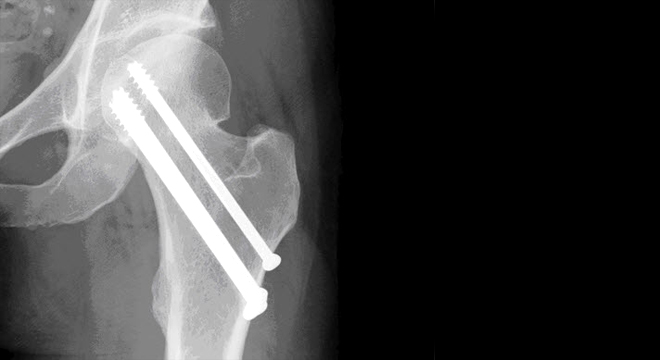

Schenkelhalsbruch: meist ist eine operative Fixation notwendig

Verschraubung (Osteosynthese): Ist nur möglich bei einer guten Knochendichte (keine Osteoporose).

Dynamische Hüftschraube (Metallplatten und Schrauben-Konstruktion): Hier wird zur Stabilisierung eine Metallplatte am Oberschenkel befestigt und eine dicke Schraube durch den Schenkelhals in den Hüftkopf gelegt. Auch diese Operation kann nur bei guter Knochendichte des Patienten vorgenommen werden.